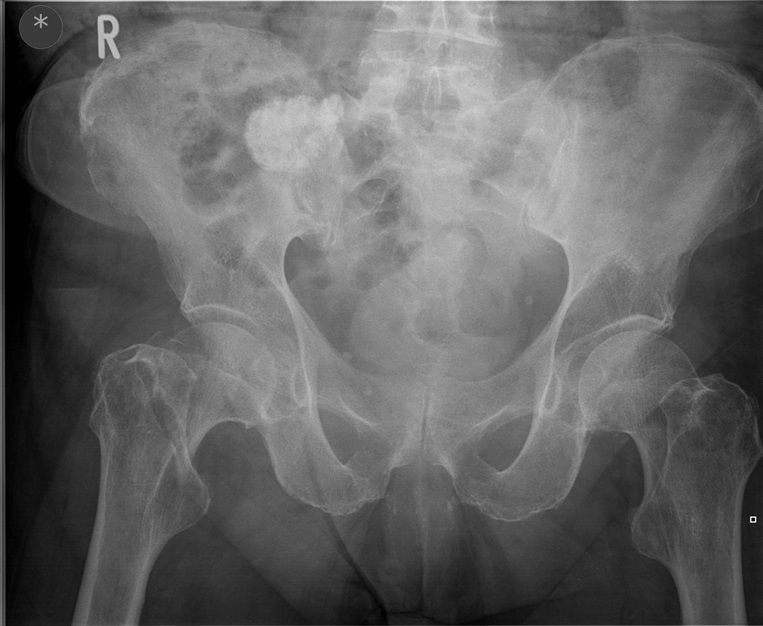

Question 3

Question

Which operation would you perform?

Answer

• THR

• Hemiarthroplasty